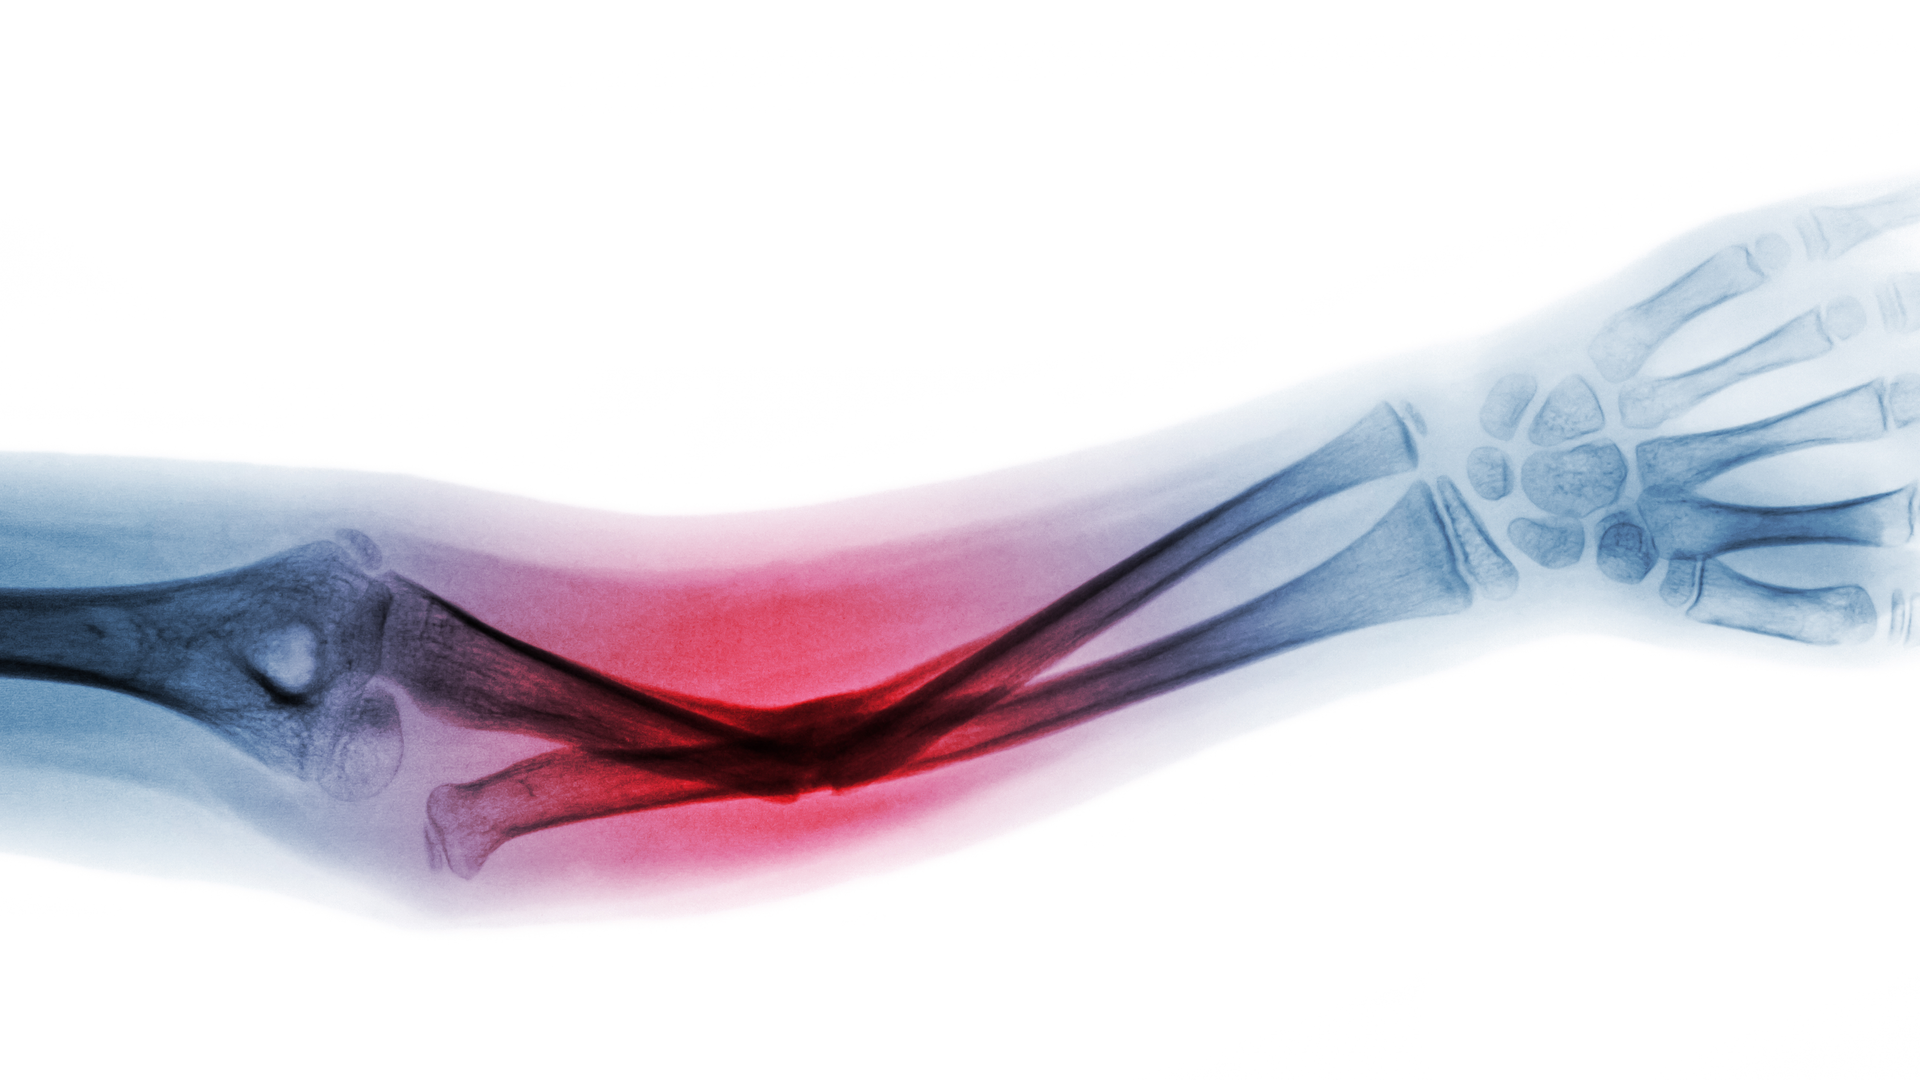

Increased fracture risk linked to high HDL-C levels

High levels of high-density lipoprotein cholesterol (HDL-C) in older adults are associated with a higher risk of sustaining a fracture than those with lower HDL-C levels, a new study suggests.

The ASPREE-Fracture substudy collected data on fractures reported post-randomization from the Australian participants. Fractures were confirmed by imaging and adjudicated by an expert panel and included both traumatic and minimal trauma fractures.